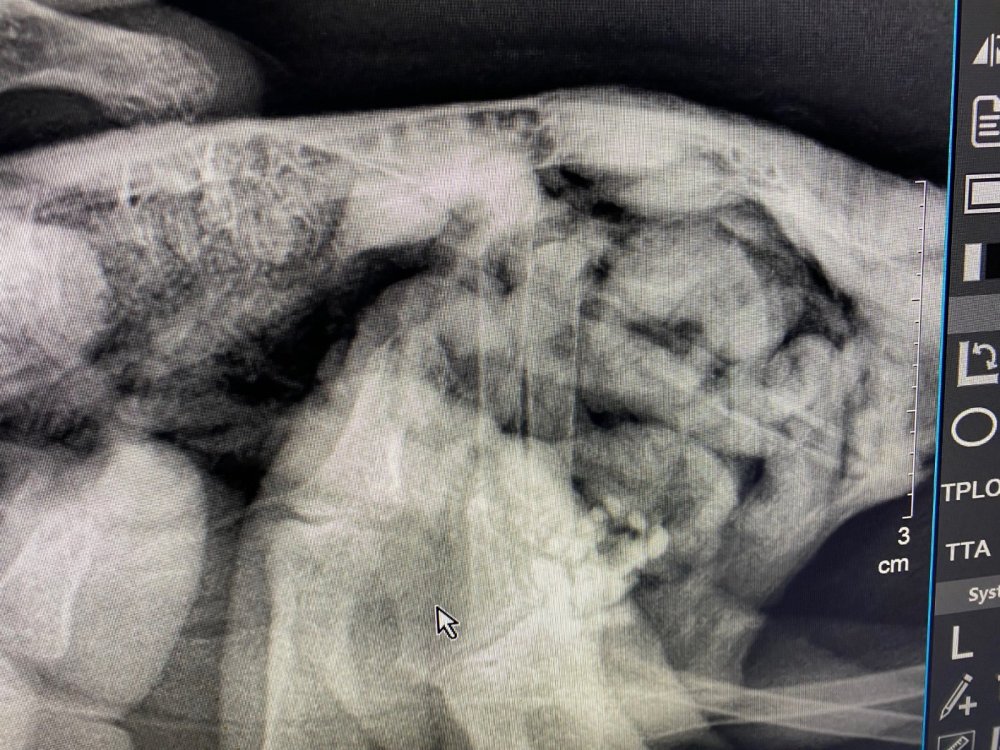

маленький принц Опубликовано 29 ноября, 2023 #126 Опубликовано 29 ноября, 2023 да у него пёрышки растут надо бы устроить купание налив в плошку чистой питьевой воды на сантиметр и затем поплескав в воде рукой чтобы он видел что там мелко и безопасно купание ОБЯЗАТЕЛЬНО под присмотром ВНИМАНИЕ сушить или греть феном птиц НЕЛЬЗЯ птицы очень легко травятся запахами горячего пластика потому что их лёгкие способны дышать разряжённым воздухом на огромной высоте В 17.10.2023 в 02:11, Анастасия Анатольевна сказал: а на лапках пока мы только так можем, попой кверху как сейчас ножки? В 29.09.2023 в 00:54, Анастасия Анатольевна сказал: @маленький принц здравствуйте! Извините пропала совсем( подходит к концу последняя неделя лечения Семен чувствует себя хорошо, на лапки не встаёт, сегодня сделали снимки ( он вырывался, поэтому держать пришлось вручную) сказали что все в норме с косточками и возможно это последствия на нервную систему какой-то инфекции и что ходить он не будет скорее всего 😭 удалось показать @Zosia рентген?